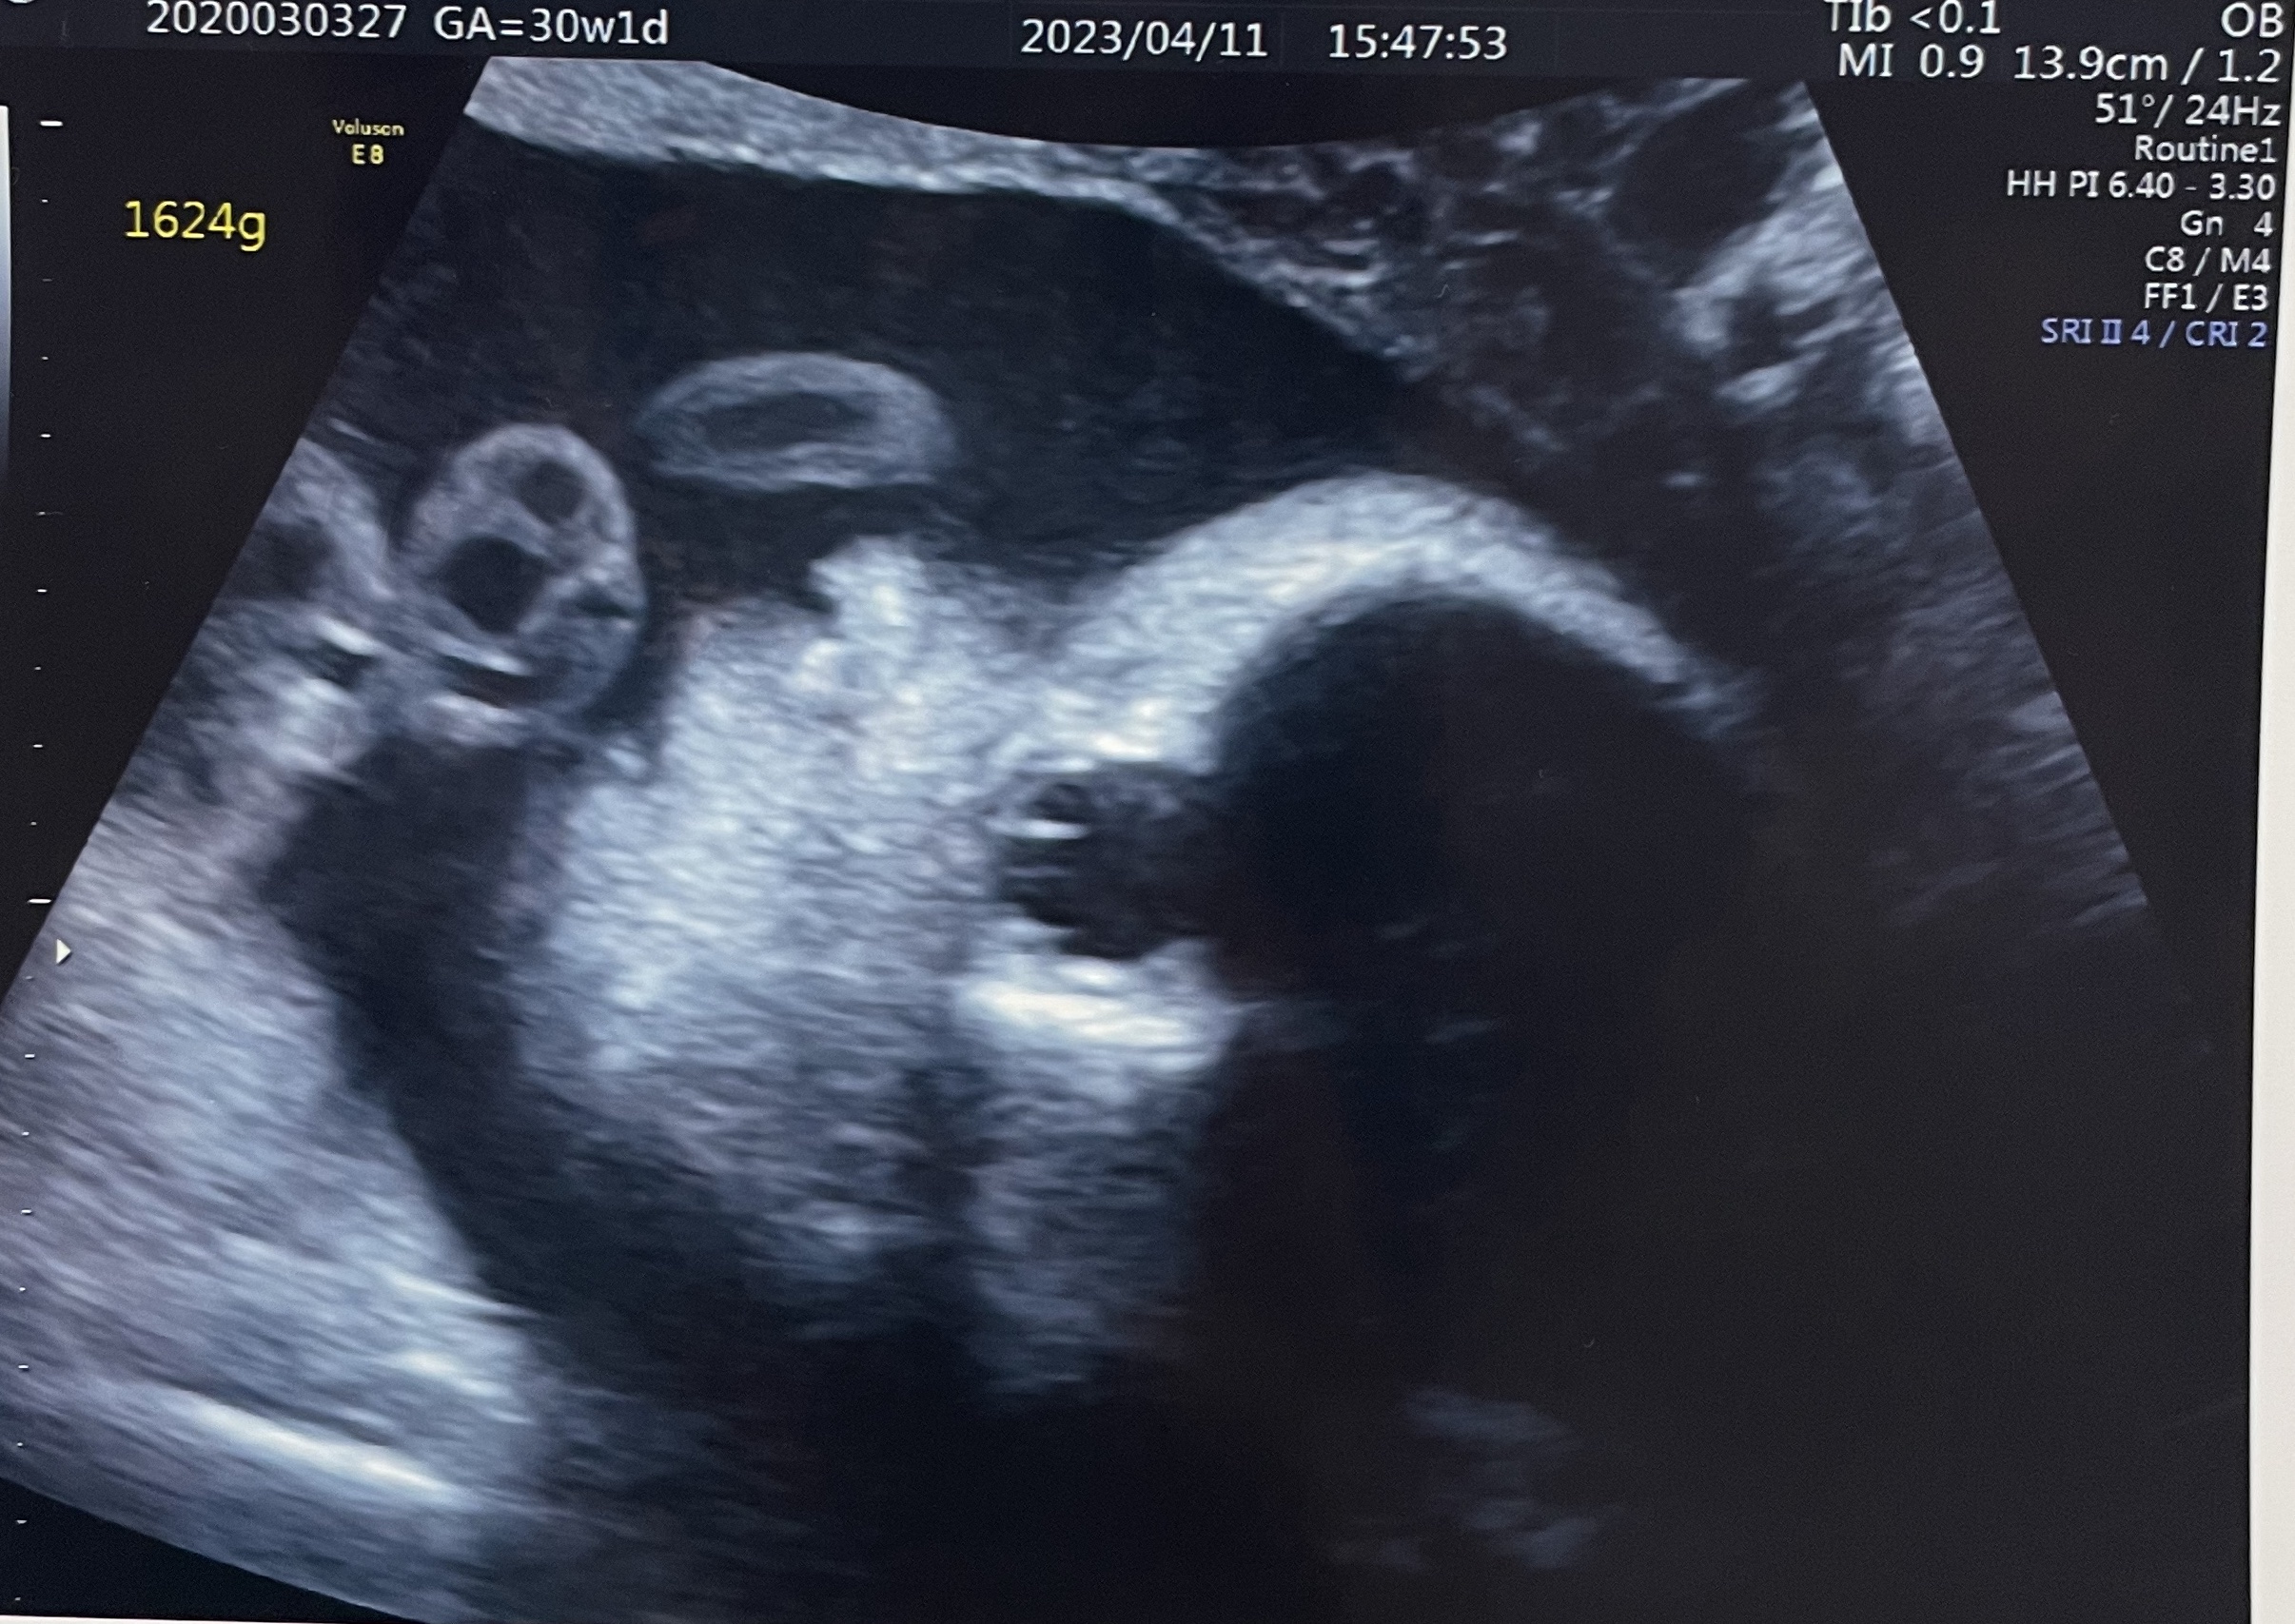

その後は、赤ちゃんの心臓の音を聞いたり、再度性別の確認などをしていただきました。性別は変わらず女の子で、今回はもう子宮を確認することもできました。(すごい!)

あとは、「ここに頭があって、今ちょうど足がお母さんの肋骨あたりにありますよ〜」など、赤ちゃんの体がわたしのお腹の中でどういうふうになっているのかも教えていただけて、なんだかほっこりする検査となりました。

今回のエコー写真でも、口の近くに手を持ってきていてすごく可愛らしい姿が見られました。